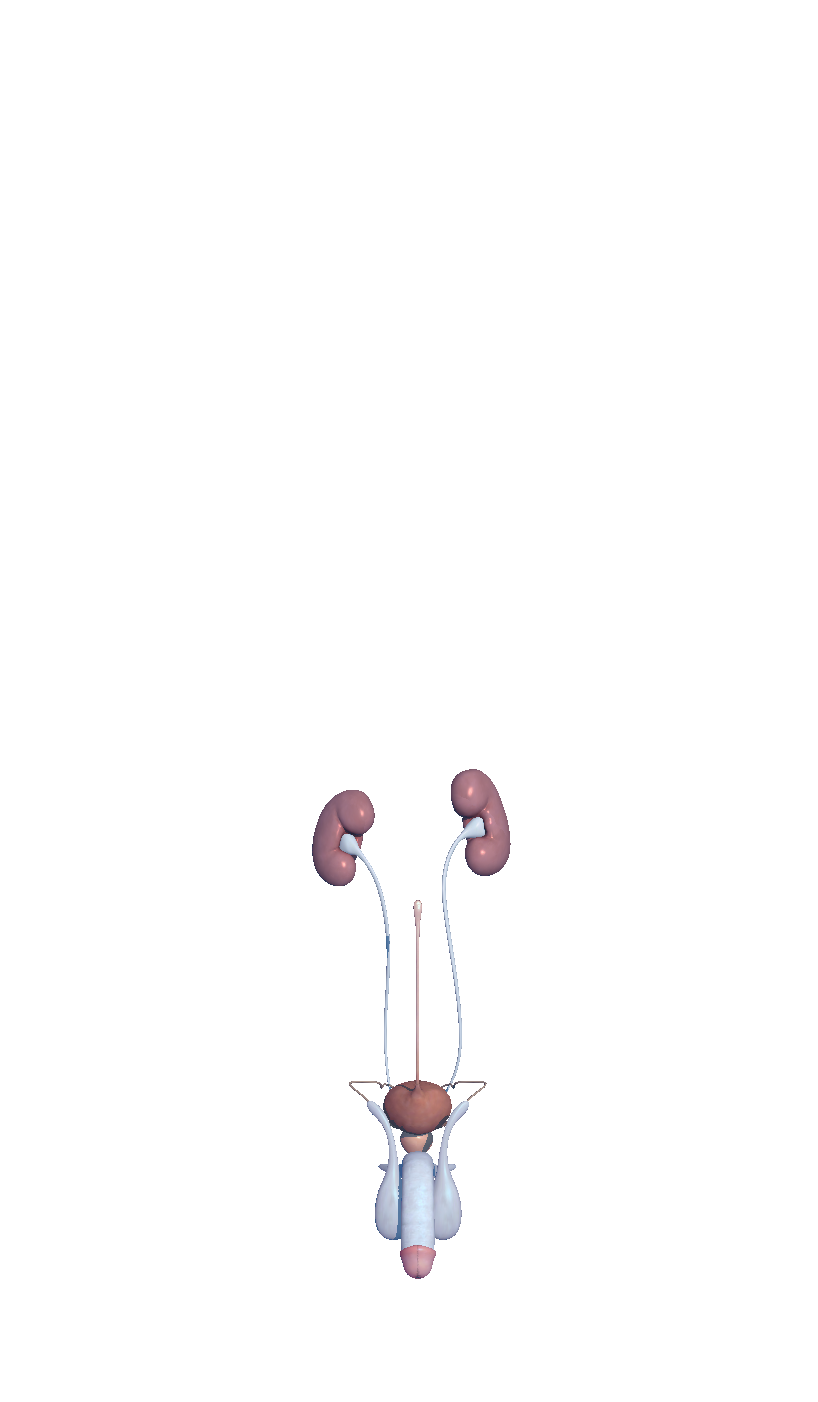

Complete and easy-to-use virtual guide for learning, understanding, and visualizing the complexities of human anatomy in 3D. Includes information and images for each anatomical system and part, multiple options to interact with the 3D anatomy models (hiding, fading, etc), and much more.

We believe that learning by interaction is the best and easiest way to study human anatomy.

- highly detailed

Hi-res imagery everywhere you need it

- Urogenital

- Urogenital